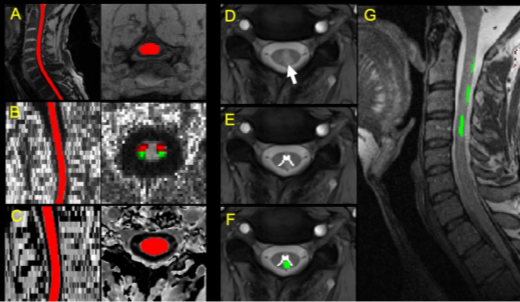

該研究是單中心臨床磁共振成像研究,運用多模態定量脊髓磁共振成像(quantitative spinal cord MRI)技術,招募了多發性硬化癥患者、MOG-Ab疾病患者、AQP4-Ab疾病患者和健康志愿者共80人,獲取其頸部等區域脊髓的截面積、病灶分布、纖維束各向異性分數和磁轉化率等多項定量指標(圖1),用于區分三種中樞神經系統脫髓鞘疾病,并評估其與殘疾指數和病理性疼痛等臨床指標的關聯性。

圖1 (A)脊髓結構分割示意,(B)各向異性分數(FA)圖、脊髓丘腦束(紅色)和皮層脊髓束(綠色),(C)磁轉化圖像分割,(D)T2* 軸位圖,顯示灰質和病灶,(E)灰質分割,(F)病灶分割,(G)病灶配準到T2結構像。